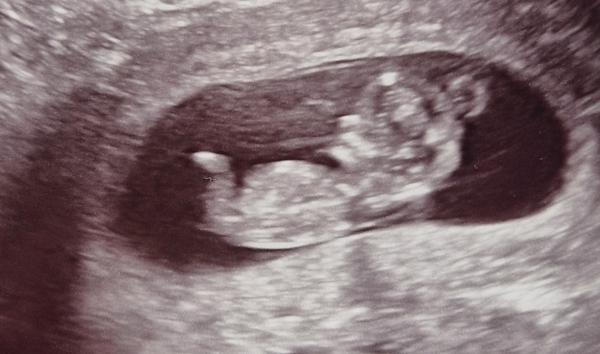

Jak odhadnout pohlaví z ultrazvuku ve 13. týdnu?

Vím, že je ještě brzo, ale zvědavost je prostě silná a když se koukám na ultrazvuk (ze 13 a 14 týdne), tak nic nemůžu poznat. 😅 Vidíte tam něco? Podle doktora na 70% kluk, ale moje intuice říká holka. U toho druhého mě to připomíná kluka, ale nejsou to jen nožičky?

Promiň ale z tohto to tedy já osobně nepoznávám. Má tam nožičky 🙂